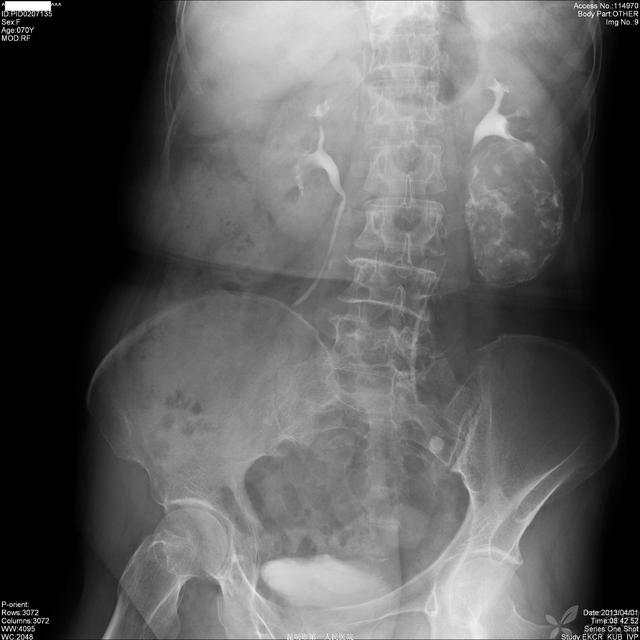

第二部分:B超

img